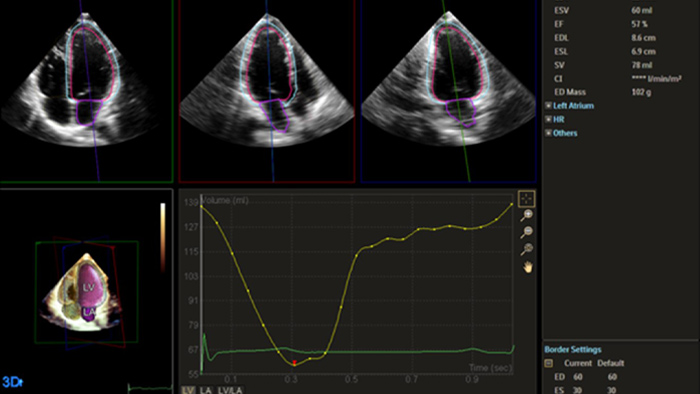

Quantification through Dynamic HeartModel.

Solution Philips IntelliSpace Cardiovascular multimodality image and information management solution offers a complete look at a patient’s cardiac history. The AI-enabled automation of Philips EPIQ CVx cardiovascular ultrasound system and Philips TOMTEC -ARENA quantification tools provides efficiency and reproducibility during echocardiography studies.

Philips solutions allow for advanced quantification and analysis, with access to information anywhere, anytime across the enterprise. AI-enabled, automated tools for visualization, analysis and streamlined reporting offer robust, reproducible results to help make the effective management of heart failure a reality.